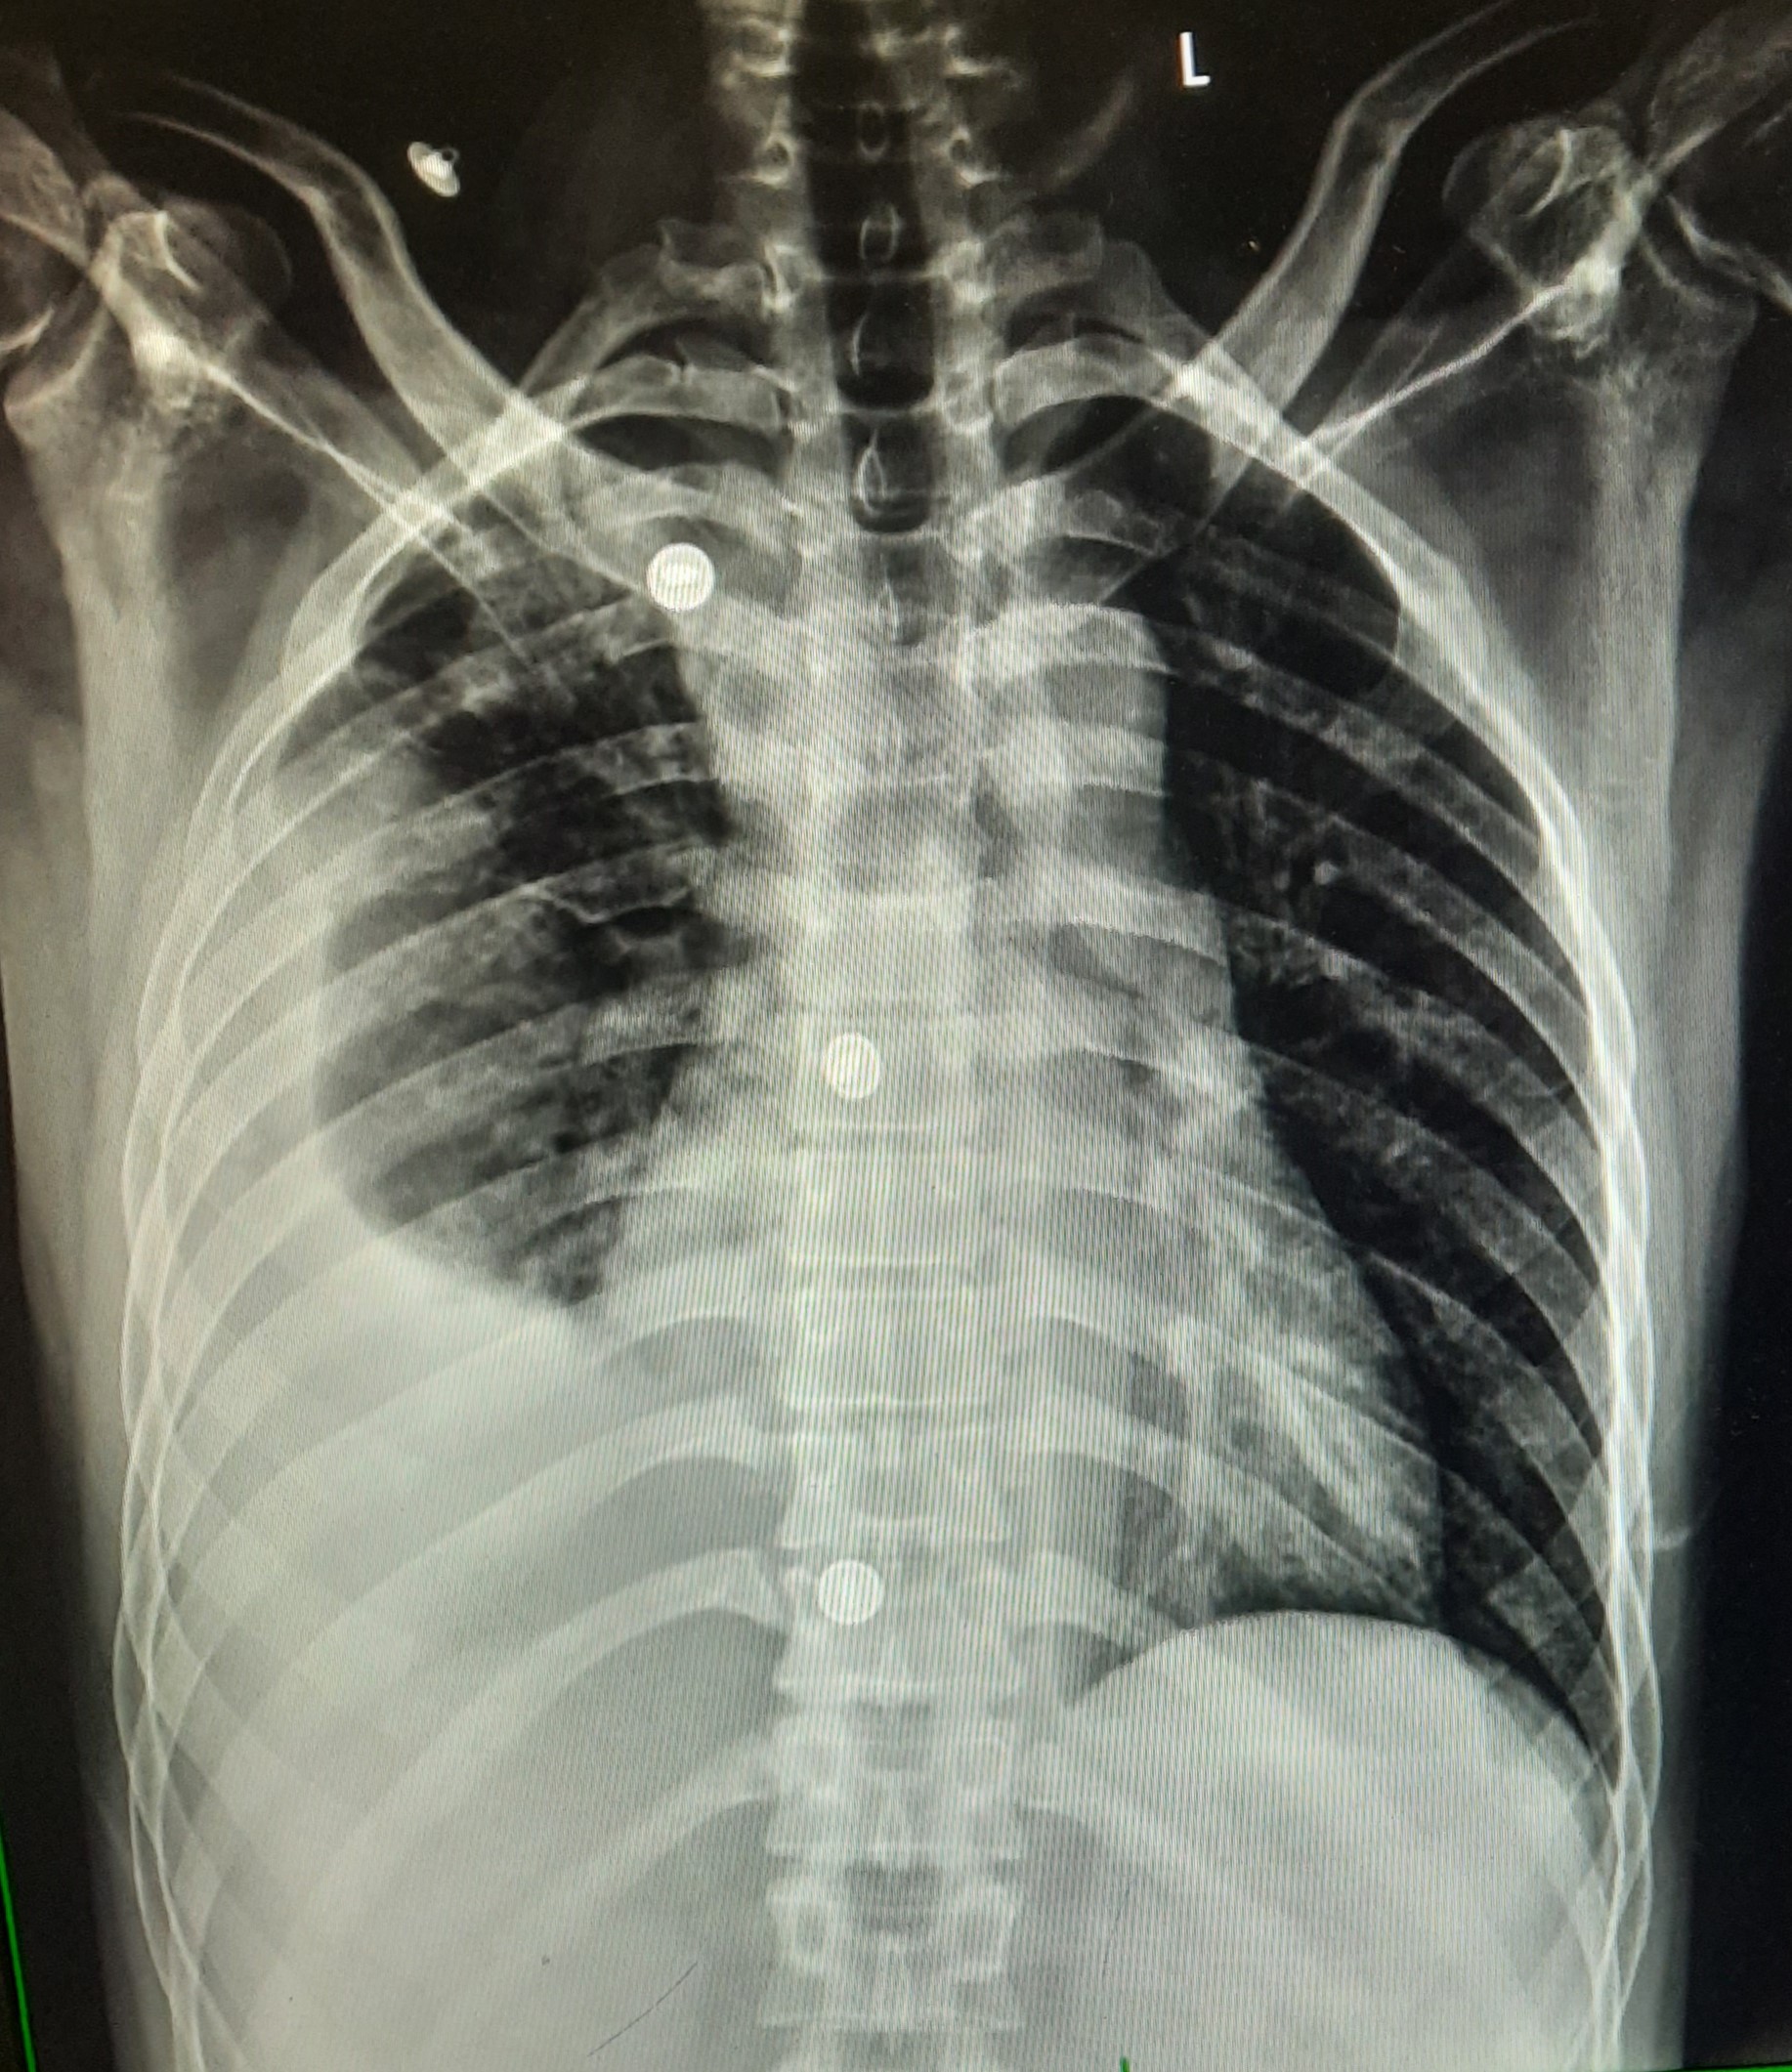

| 54 | IGGMC, Nagpur, Nagpur | P2 | 29-4418 | Pradip Bankar | Consent taken on Paper | 37 Yrs. |

Provisional Diag : Pulmonary Tuberculosis

Final Diag : Pulmonary Tuberculosis (Microbiologically Confirmed PTB) |

TB Case (Confirmed) | Left upper Zone Fibro cavitary lesion Present, Bilateral Lung Infiltration present | Abnormality visible on x-ray |